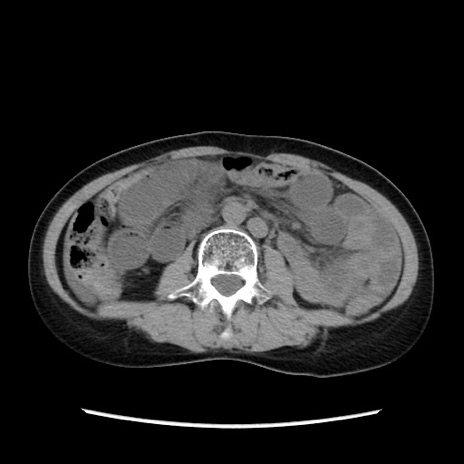

症例32(横断像)

【症例】40歳代 女性

【主訴】上腹部痛、嘔気・嘔吐

【現病歴】約9時間前頃から急に上腹部痛、嘔気、嘔吐が出現。改善しないため救急要請。

【既往歴】子宮頚癌(広汎子宮全摘術、放射線療法)、腸閉塞

【身体所見】腹部:平坦、軟、腸雑音亢進、上腹部を中心に腹部全体に圧痛あり。

【データ】WBC 8400、CRP 0.03